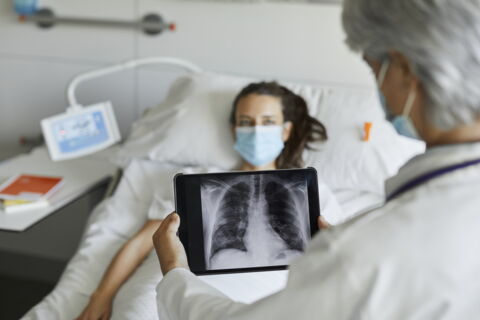

Jetzt transplantierte ein Roboter einer Frau eine Lunge.

Sie ist die erste Patientin, der beide Lungenflügel von einem Roboter transplantiert wurden!

Die Rede ist von Cheryl Mehrkar aus den USA.

Die 57-Jährige wurde sieben Stunden lang im NYU Langone Health Center Transplant Institute operiert, einer “Spezialklinik” in New York, so die Bild.

Die OP erfolgte am 22. Oktober 2024.

Durchgeführt wurde die Operation von Dr. Stephanie H. Chang, einer außerordentlichen Professorin der Abteilung für Herz- und Thoraxchirurgie an der NYU Grossman School of Medicine, so die Quelle weiter.